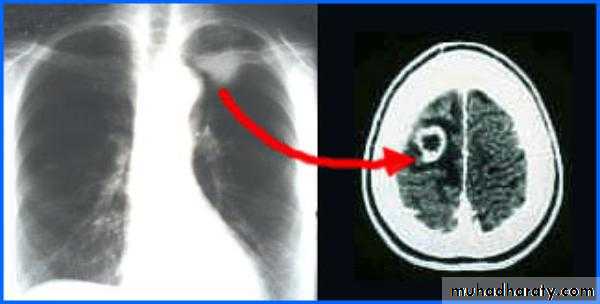

• 35% - lung

• Computed Tomography scan (CT scan) with/without contrast• Magnetic Resonance Imaging (MRI) with/without contrast